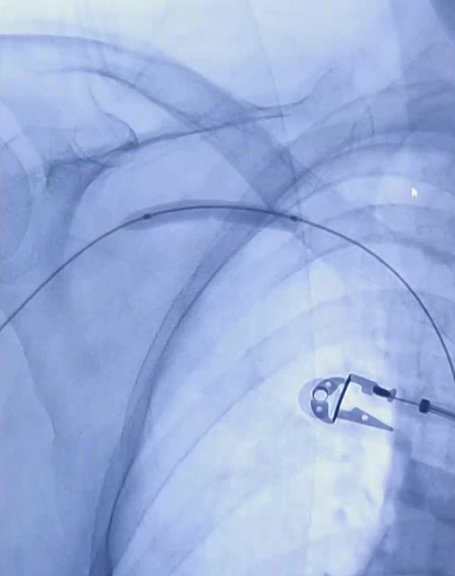

3/ 选用6mm×40mm及8mm×60mm ZENFLOW® HP(归创)球囊扩张导管依次扩张头静脉弓狭窄段;

6mm×40mm